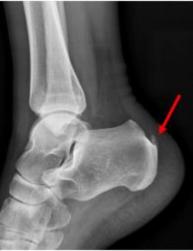

跟腱炎的不同位置跟腱炎通常发生在跟腱止点处或跟腱的中段。跟腱反复微创伤,会引起肌腱钙盐沉积,导致跟腱钙化。跟腱钙化后,可能出现不能长时间站立、走路疼痛、跟腱水肿等症状。

跟腱钙化(X光片)3、患有跟腱炎该怎么办?

跟腱断裂的诊断主要依据患者的病史、体格检查(腓肠肌试验),以及超声检查和MRI检查,可以清晰显示断裂部位。